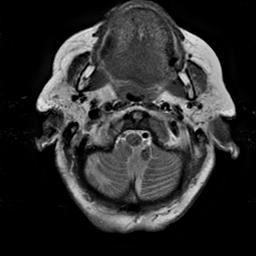

To demonstrate the effectiveness and efficiency of the proposed image fusion method , we conduct a set of comparative experiments on three image datasets. The first is composed by 8 pairs of multi-modal medical images and the second one contains 15 pairs of multi-focus gray or color natural images. These two datasets are often used in many related papers and some examples are shown in Figure 3(a) and Figure 3(b). The third one is a new multi-focus cervical cell image dataset collected by ourselves, which consists of 15 groups of color images and each group contains a series of multi-focus cervix cell images with size of or , etc. Some source examples are shown in Figure 3(c). Our source code implemented in C++ along with the new multi-focus cervical cell image dataset is available online.

We first evaluate the performance of the proposed method under varying total number of octaves and number of layers sampled per octave. The fused images of a pair of multi-modal medical images with different and are shown in Figure 4. In this example, on the one hand, when only 1 or 2 octaves are involved in constructing the DoG pyramid, the fused images fail to keep the integrity information of large size objects (e.g. eyeballs), while by increasing the value of , the integrity information of eyeballs is preserved. On the other hand, although not as significant as the increase of octave numbers , the fused image can contain more details by the increase of layer numbers . The corresponding objective quality metrics are shown in Figure 5. As shown in Figure 5(a), most of the metric values are improved as the number of octaves increases with the fixed layer numbers 3 in the global tendency and each of them tends to be stable when the number of octaves is 5. To get a relatively good quality from Figure 5(b), we can notice that some of the metric values can get a good performance when the number of layers is 3, such as the MI, SSIM, QI and VIF, though there are only a little change of all the metric values by increasing the number of layers with the fixed octave numbers 5. Because it will result in more computation burden with the increase of the value and , and for different kinds of source images, there are different performance with the diverse parameter settings. To get a trade-off between them in our experiments, we set for the multi-modal dataset, for the natural datasets and for the multi-focus cell dataset, respectively.

Figure 6 shows the fused images obtained by different methods with the multi-modal source images shown in Figure 3(a). As shown in these figures, the proposed method can produce images which preserve the complementary information of different source images well. Moreover, due to the scale-invariant structure saliency selection, our method can keep the integrity information of large size objects and the visual details simultaneously. Although the fused image generated by other methods can also capture the details to some extent, all of them fail to keep the integrity information of large size objects such as the eyeballs. Furthermore, from Figure 6(k)-6(t), the DTCWT, GFF, IM and NSCT methods may decrease the brightness and contrast while the proposed method can preserve these features and details without producing visible artifacts and brightness distortions.